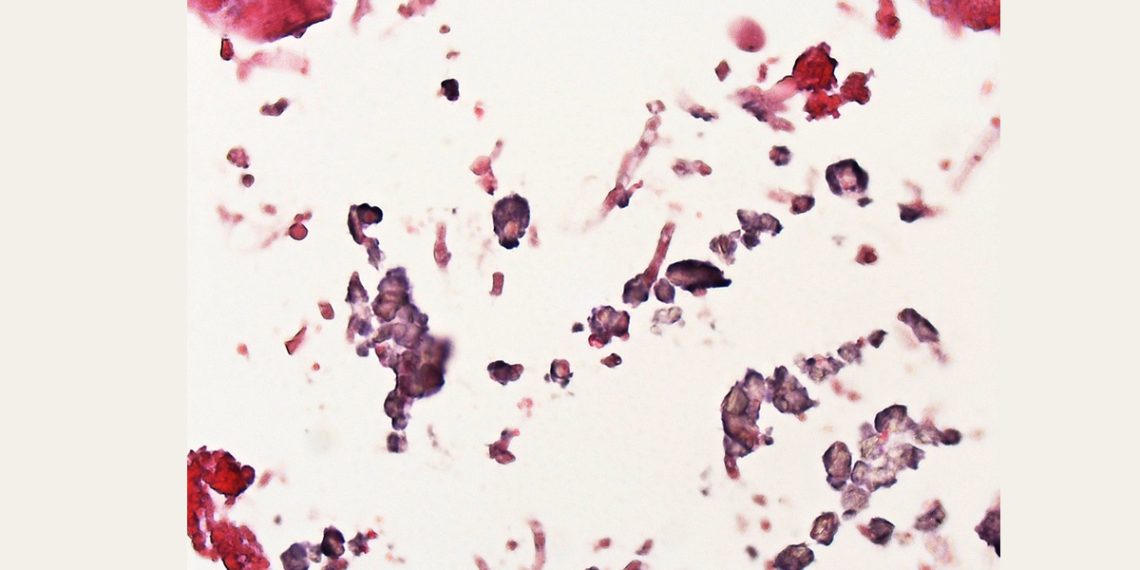

5. Histopathology

- Invasive aspergillosis may require tissue biopsy to confirm fungal invasion

- Collects fluid and tissue samples for biopsy and fungal staining